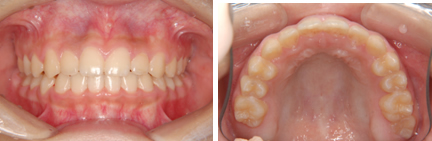

3.中・高校生の治療 (永久歯列)

中・高校生(歯のデコボコ) 13歳

治療前(抜歯ナシ)

治療後(期間:約1年6ヶ月~2年)

※この治療には個人差があります

①主訴:八重歯を治したい

②診断名あるいは主な症状:前歯部叢生

③年齢:13歳

④治療に用いた主な装置:マルチブラケット装置

⑤抜歯部位:写真の症例は非抜歯(かみ合わせや叢生の程度により抜歯が必要となる場合もある)

⑥治療期間:1年半~2年半

⑦治療費:検査:49,500円

基本矯正費用:880,000円~

調整料:6,600円(ひと月に1回)

⑧リスクと副作用:治療開始後数日は噛むときに痛みがあります。

虫歯や歯肉炎予防のために毎日の適切な歯磨きが重要。

装置が破損する場合があり、その時は連絡が必要

治療後には後戻り防止として保定装置が必要

歯の移動により歯根の先が溶ける場合がまれにある。